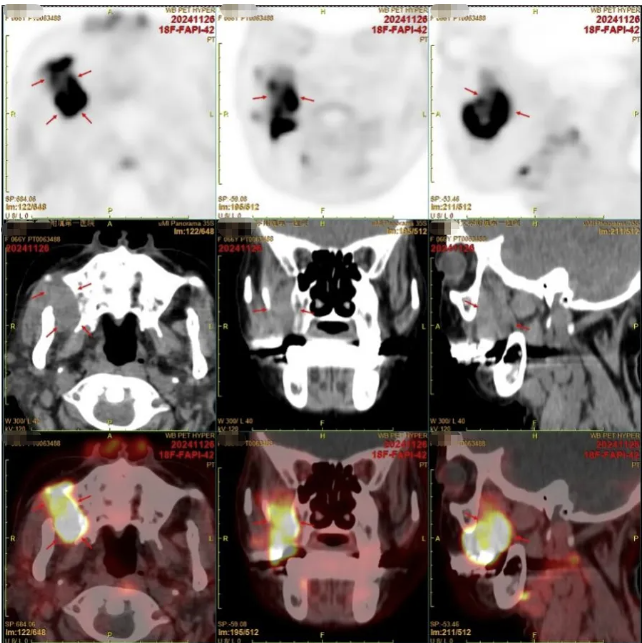

鉴于目前检查未能明确病因,经全院MDT讨论后建议再次完善FAPI-PET-CT明确病因。

11月26日,再次行全身FAPI-PET-CT检查提示:1.右侧颞下部 FAP 高摄取肿块影,考虑为恶性肿瘤(间叶来源恶性肿瘤?恶性淋巴瘤?),建议核医学科分子影像PET/CT引导下穿刺活检(活部位见图)。2.双肺各叶多发结节、斑片及团块状实变病灶,FAPI摄取明显增高,对比外院2024-10-16PET/CT数目较前增多、范围较前增大,考虑为双肺多发转移瘤。3.双侧颈部(I、II区)、双侧肺门、纵隔内、双侧腋窝、左侧内乳区、心膈角区多发增大淋巴结。部分FAPI摄取增高,考虑为多发淋巴结转移。患者12月2日右侧颌面部活检病理结果回报:B细胞淋巴瘤,倾向弥漫大B淋巴瘤。骨穿结果:送检骨髓组织增生大致正常,三系均可见,粒红系大致正常,均以中晚幼阶段为主,巨核可见,以成熟分叶核为主,未见肿瘤。

图7:右侧颌面部病灶较前明显增强